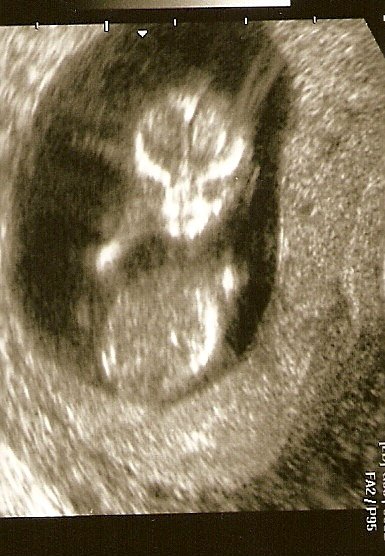

Kép

Itt van az én kisfiam és épp integet.kicsit átméreteztem, mert nagy volt a mérete.remélem azért kivehető a picike. :D

Itt épp 12 hetesek vagyunk.

Cuki az integetős kép! És szépen látszódnak a fejecskéjén a szem-, orr-, és homloküregek. Ez jó jel!